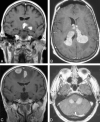

CNS lymphoma consists of 2 major subtypes: secondary CNS involvement by systemic lymphoma and PCNSL. Contrast-enhanced MR imaging is the method of choice for detecting CNS lymphoma. In leptomeningeal CNS lymphoma, representing two-thirds of secondary CNS lymphomas, imaging typically shows leptomeningeal, subependymal, dural, or cranial nerve enhancement. Single or multiple periventricular and/or superficial contrast-enhancing lesions are characteristic of parenchymal CNS lymphoma, representing one-third of secondary CNS lymphomas and almost 100% of PCNSLs. New CT and MR imaging techniques and metabolic imaging have demonstrated characteristic findings in CNS lymphoma, aiding in its differentiation from other CNS lesions. Advanced imaging techniques may, in the future, substantially improve the diagnostic accuracy of imaging, ultimately facilitating a noninvasive method of diagnosis. Furthermore, these imaging techniques may play a pivotal role in planning targeted therapies, prognostication, and monitoring treatment response.